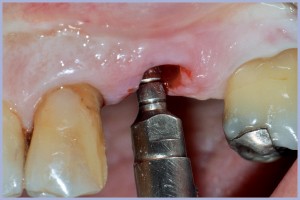

- Fig. 34 – Inserimento impianto Exacone® Max Stability Ø 4,5 mm sede 14

- Fig. 35 – Connessione del moncone definitivo su impianto 14